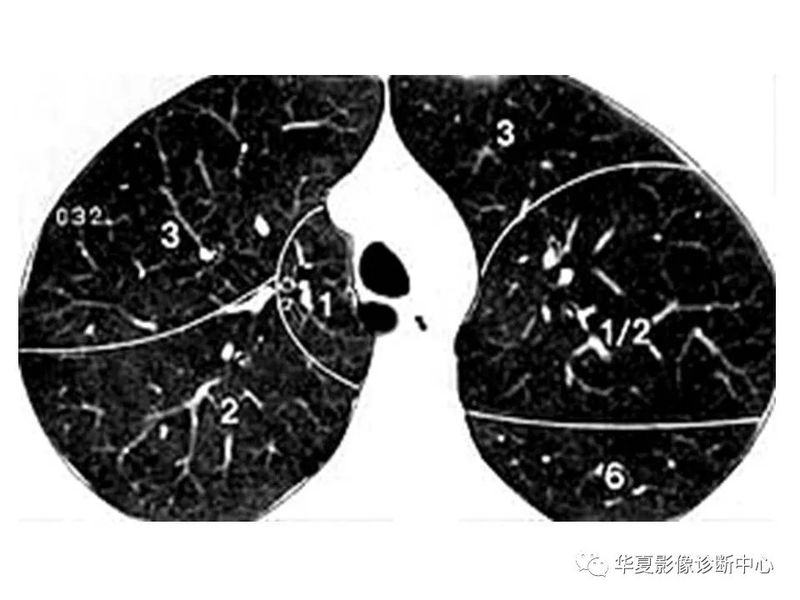

干货 | 汇总胸部CT读片扫盲知识,看懂胸部CT不再难